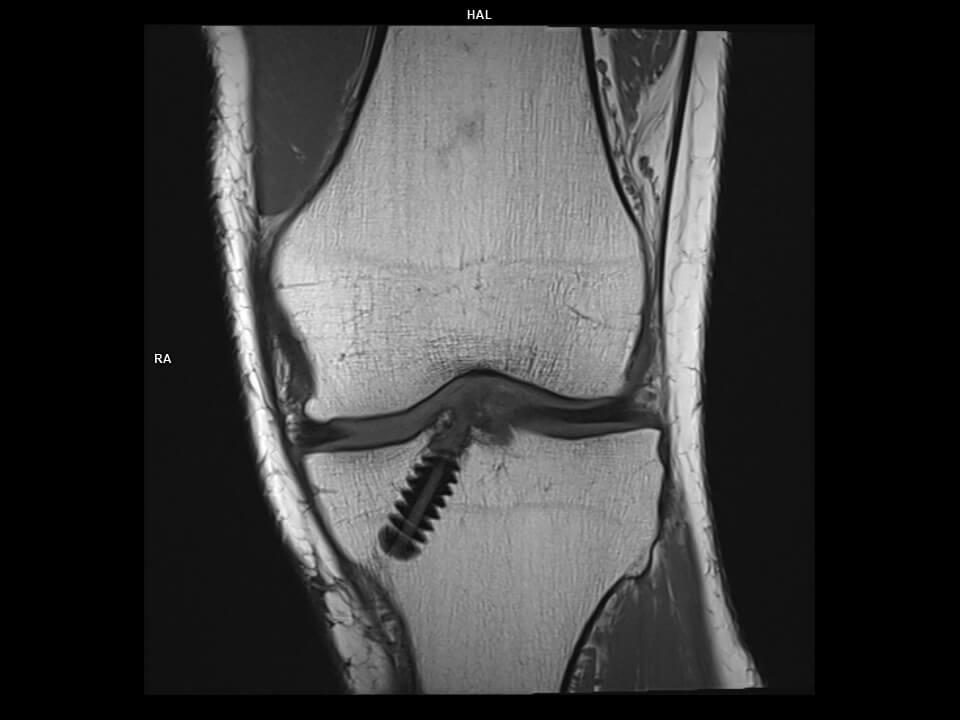

CORONAL T1 TSE-MAGNETOM Vida

CORONAL T1 TSE-MAGNETOM Vida/TxRx 18CH KNEE COIL/Resolution-512/Scan Time-3:20/Aceleration-p2